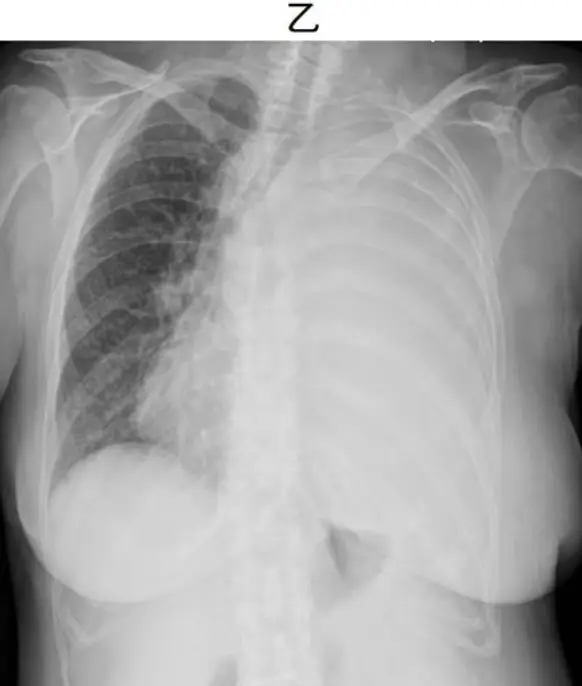

病人甲與病人乙皆主訴左胸悶、呼吸喘促,其胸部 X 光發現兩人的左胸廓都幾乎全白,如圖(三)。如果單以 X 光判讀來決定,是否適合為病人進行胸管引流來減輕其症狀,請問下列何項決策正確?

- 病人乙(B):左側全白,同時左心膈角消失,伴有縱隔(氣管)向右側明顯偏移;高度提示大量 pleural effusion 產生質量效應(mass effect),符合 massive pleural effusion (radiopaedia.org)。